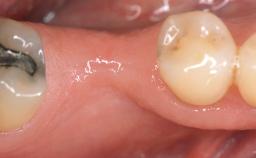

A 30-year-old woman was referred by her general dentist for evaluation of an esthetic complication related to previous implant treatment for congenitally missing maxillary lateral incisors. The patient’s chief complaint was the inadequate esthetic appearance of her smile. The case demonstrates the use of a combined approach to achieve optimal results. Two different flap designs - a tunnel technique and a coronally advanced flap - are employed based on the surgical objectives for the affected site.

Jaw Maxilla

Area Anterior

Soft Tissue Grafting Yes